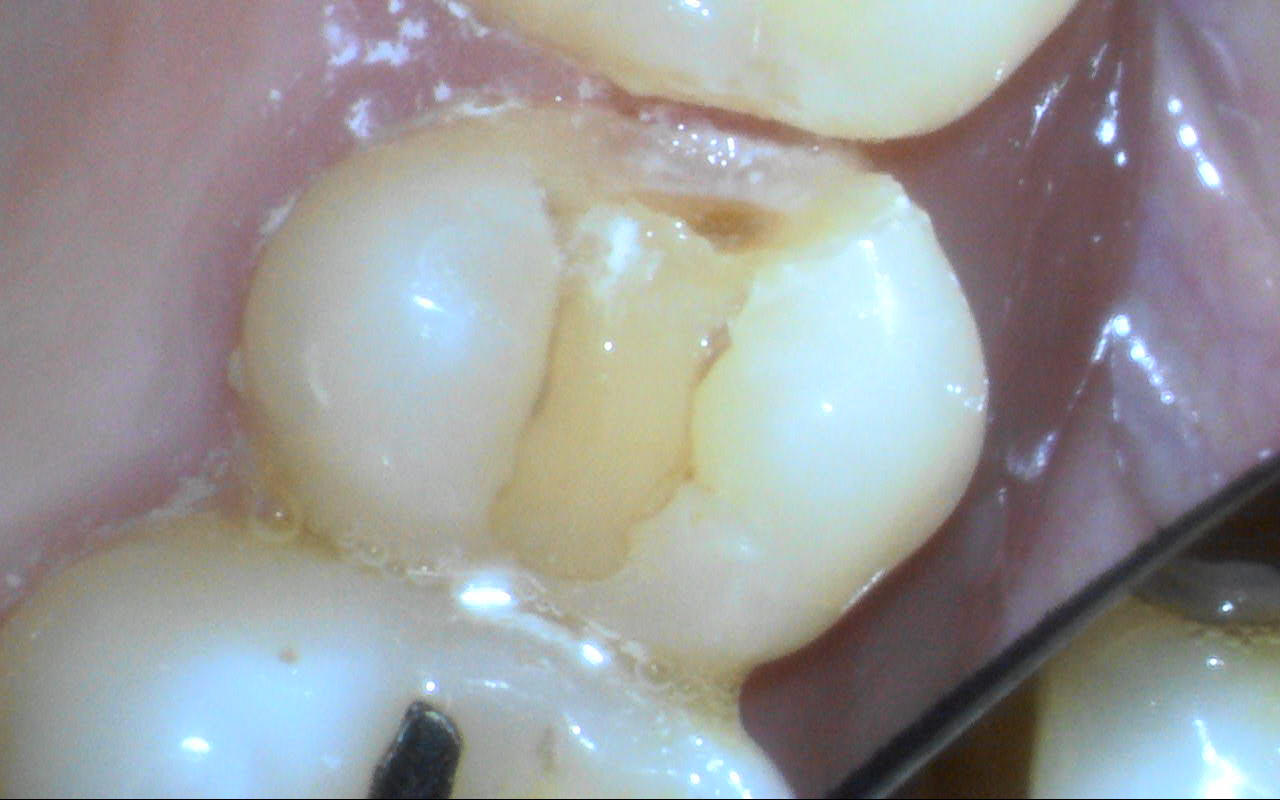

6〜7年前に治療した右上の歯が、噛むと痛むとのことで来院されました。細かく診査したところ、歯の一部に圧痛があり、マイクロスコープで拡大して確認したところ、詰め物に細かなヒビが認められました。

痛みのある部分を慎重に確認したところ、以前に装着された詰め物が割れていることが確定しました。